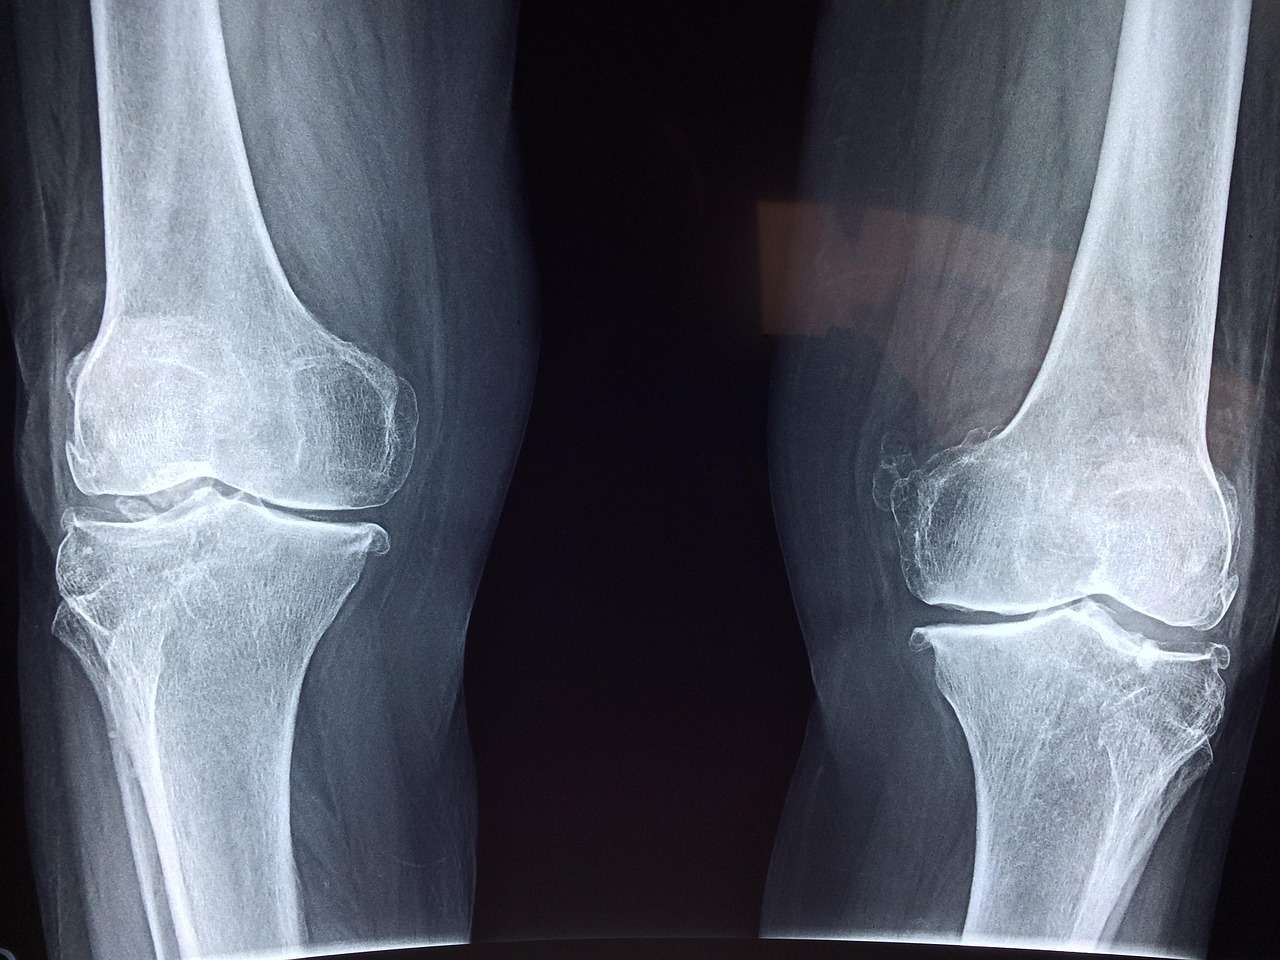

특히 40대 후반부터는 관절 연골이 자연스럽게 닳기 시작하며, 50~60대에 접어들면 무릎 관절염, 연골연화증, 반월상연골 손상 같은 질환이 본격적으로 나타날 수 있습니다.

- 퇴행성 관절염: 연골이 점점 닳아 없어지면서, 뼈끼리 직접 마찰하며 통증 유발